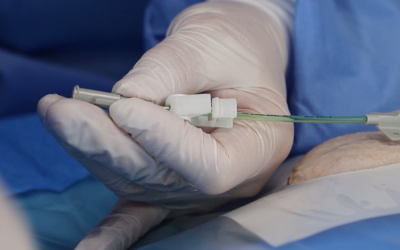

Colocación del puerto venoso

3. Acceso por la vena subclavia en adultos

Además, no es necesario tunelizar, es un abordaje más cómodo et rápido.

Hoy en día, nuestra vía de abordaje de elección era la vena subclavia en el surco deltopectoral, lo cual permite una gran discreción para los pacientes (respeto del escote). Colocamos el 99% de nuestros puertos con este abordaje.

Se punciona la vena en el fondo del bolsillo: de esta manera el catéter tiene un recorrido más fisiológico y evitamos los posibles curvas o acodamientos que pueden crearse cuando la vena se punciona desde otro lugar.